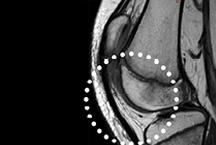

Antes e Depois da Terapia por Ondas de Choque Focal

Antes

Depois

TENDINOPATIA PATELAR, CORTESIA: BTL